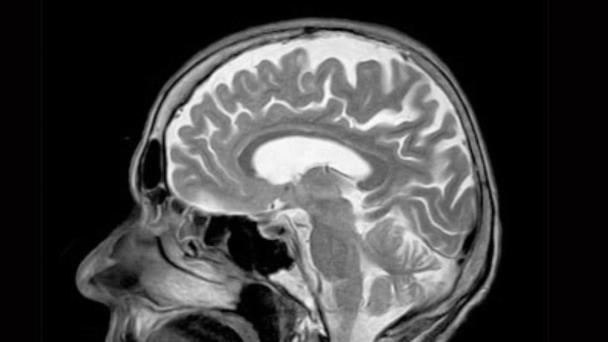

El abanico de conductas es amplio, pero todos los psicópatas coinciden en una cosa: las alteraciones cerebrales que los diferencian de otros individuos sin este trastorno. Pujol y su equipo revisaron más de 400 artículos científicos en los que se había analizado el cerebro de las personas con psicopatía a través de resonancias magnéticas. El metaanálisis, publicado en la revista científica Psychological Medicine, ha concluido que el cerebro de los psicópatas presenta una maduración acelerada de varias regiones cerebrales relacionadas con el procesamiento emocional y el cognitivo. "El cerebro de los psicópatas es diferente desde el punto de vista anatómico y funcional. Hay diferencias en las áreas que procesan la cognición y el razonamiento y en las que procesan la actividad emocional. La conexión entre estas dos áreas falla", explica Pujol.

Los investigadores encontraron que, desde el punto de vista anatómico, en las regiones de lóbulo temporal (donde está la amígdala, relacionada con la emociones) y en el frontal (encargado de las funciones cognitivas) había "una aparente atrofia de la sustancia gris". "Sin embargo, lo que luego nosotros postulamos es que, en realidad, lo que había era un aumento de la sustancia blanca, lo que implica una sobremaduración de esas áreas", apunta Pujol.